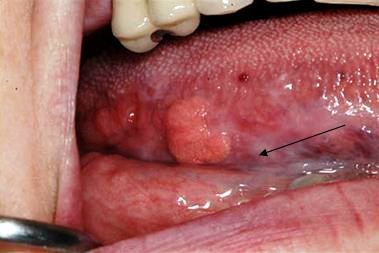

These papules are characteristic of focal epithelial hyperplasia (Heck disease). This condition is caused by HPV-13 and HPV-32.

Photo courtesy of Dr Dolphine Oda.